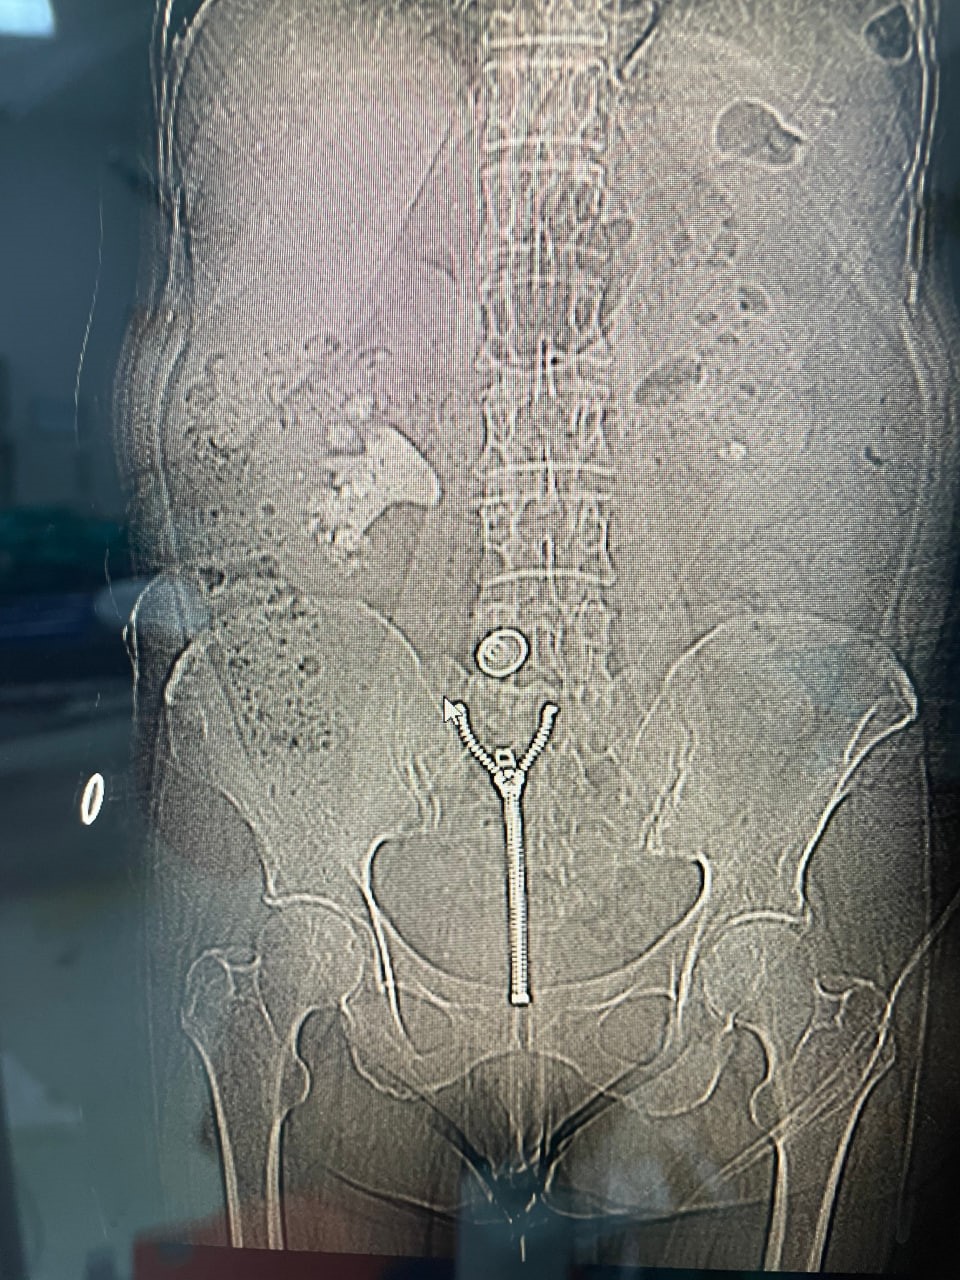

Malatya Eğitim ve Araştırma Hastanesi’nde 58 yaşındaki Ülkü Sabaner’in böbreğini tamamen dolduran 8 santimetrelik "geyik boynuzu" (staghorn) böbrek taşı, kapalı yöntemle gerçekleştirilen başarılı bir operasyonla çıkarıldı.

Sağ yan ağrısı şikâyetiyle hastaneye başvuran Sabaner’in yapılan tetkiklerinde, sağ böbreğini neredeyse tamamen dolduran büyük boyutlu bir taş olduğu belirlendi. Daha önce de böbrek taşı nedeniyle tedavi gören ve çocukluk yaşlarından itibaren taş hastalığıyla mücadele ettiği öğrenilen hastaya, Üroloji Kliniği uzmanları tarafından kapalı ameliyat önerildi.

Operasyonu gerçekleştiren Üroloji Kliniği Uzmanı Dr. Mehmet Levent Akbulut, taşın büyüklüğüne dikkat çekerek, "Hastamızın böbreğinde yaklaşık 8 santimetre çapında büyük bir taş vardı. Tıpta bu tabloya ‘staghorn’, yani geyik boynuzu taşı diyoruz. Eğer bu taş alınmasaydı, böbrek fonksiyonunu tamamen kaybedebilirdi. Biz de perkütan nefrolitotomi adını verdiğimiz kapalı yöntemi tercih ettik. Tomografi yardımıyla planlama yaparak, böbreğe küçük bir delikten girip taşı parçalara ayırarak tamamen temizledik. Ameliyat sonrası hastamızın böbreği taşsız hale getirildi" dedi. Dr. Akbulut, söz konusu yöntemin açık ameliyata göre çok daha hızlı iyileşme süreci sağladığını ve bu tür kompleks operasyonların Malatya’da başarıyla gerçekleştirilebildiğini belirtti.